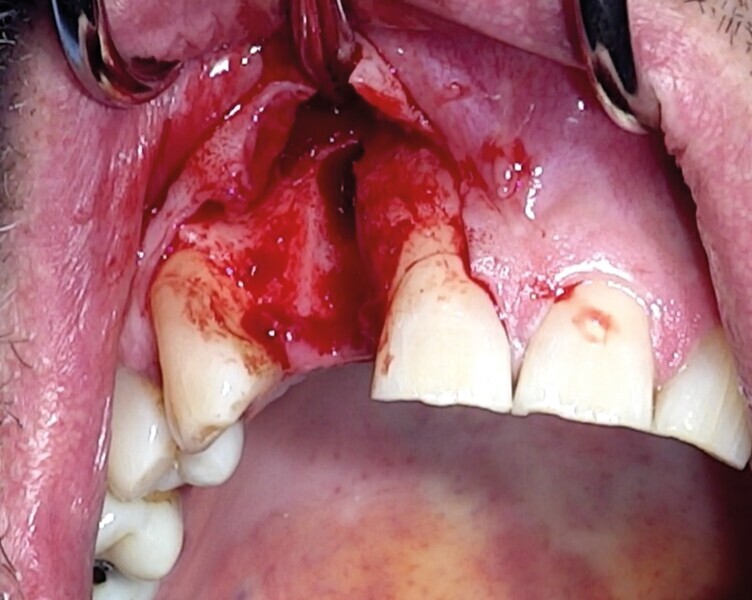

Une fracture radiculaire de 22 a lésé la table osseuse vestibulaire et la gencive en regard. Elle est extraite minutieusement à l’aide du Benex (Fig. 19). Un curetage de l’alvéole est réalisé manuellement puis au contra-angle, à l’aide d’une fraise boule multilame de gros diamètre. Un lambeau de pleine épaisseur est soulevé (Fig. 20).

Comme la technique initiale, le défaut osseux est calibré par un trépan (Fig. 21) d’extraction-implantation immédiate, plus apicale que l’apex de l’alvéole dentaire et aux dépens de la corticale palatine.

Dans certaines situations cliniques, l’étude radiologique tridimensionnelle montre un volume osseux exploitable en position de 18 ou 28. Il est alors aisé de réaliser le prélèvement au trépan, sur ces sites habituellement larges. Toute la pertinence dans ce cas est de le réaliser à travers la gencive kératinisée et obtenir ainsi une carotte ostéo-gingivale (Fig. 22). De ce fait, il ne faut pas faire d’incision ou de lambeau pour ouvrir l’accès au trépan. Le geste devient extrêmement rapide mais nécessite une bonne connaissance anatomique, une excellente analyse de la planification 3D, puis un bon repérage clinique.6